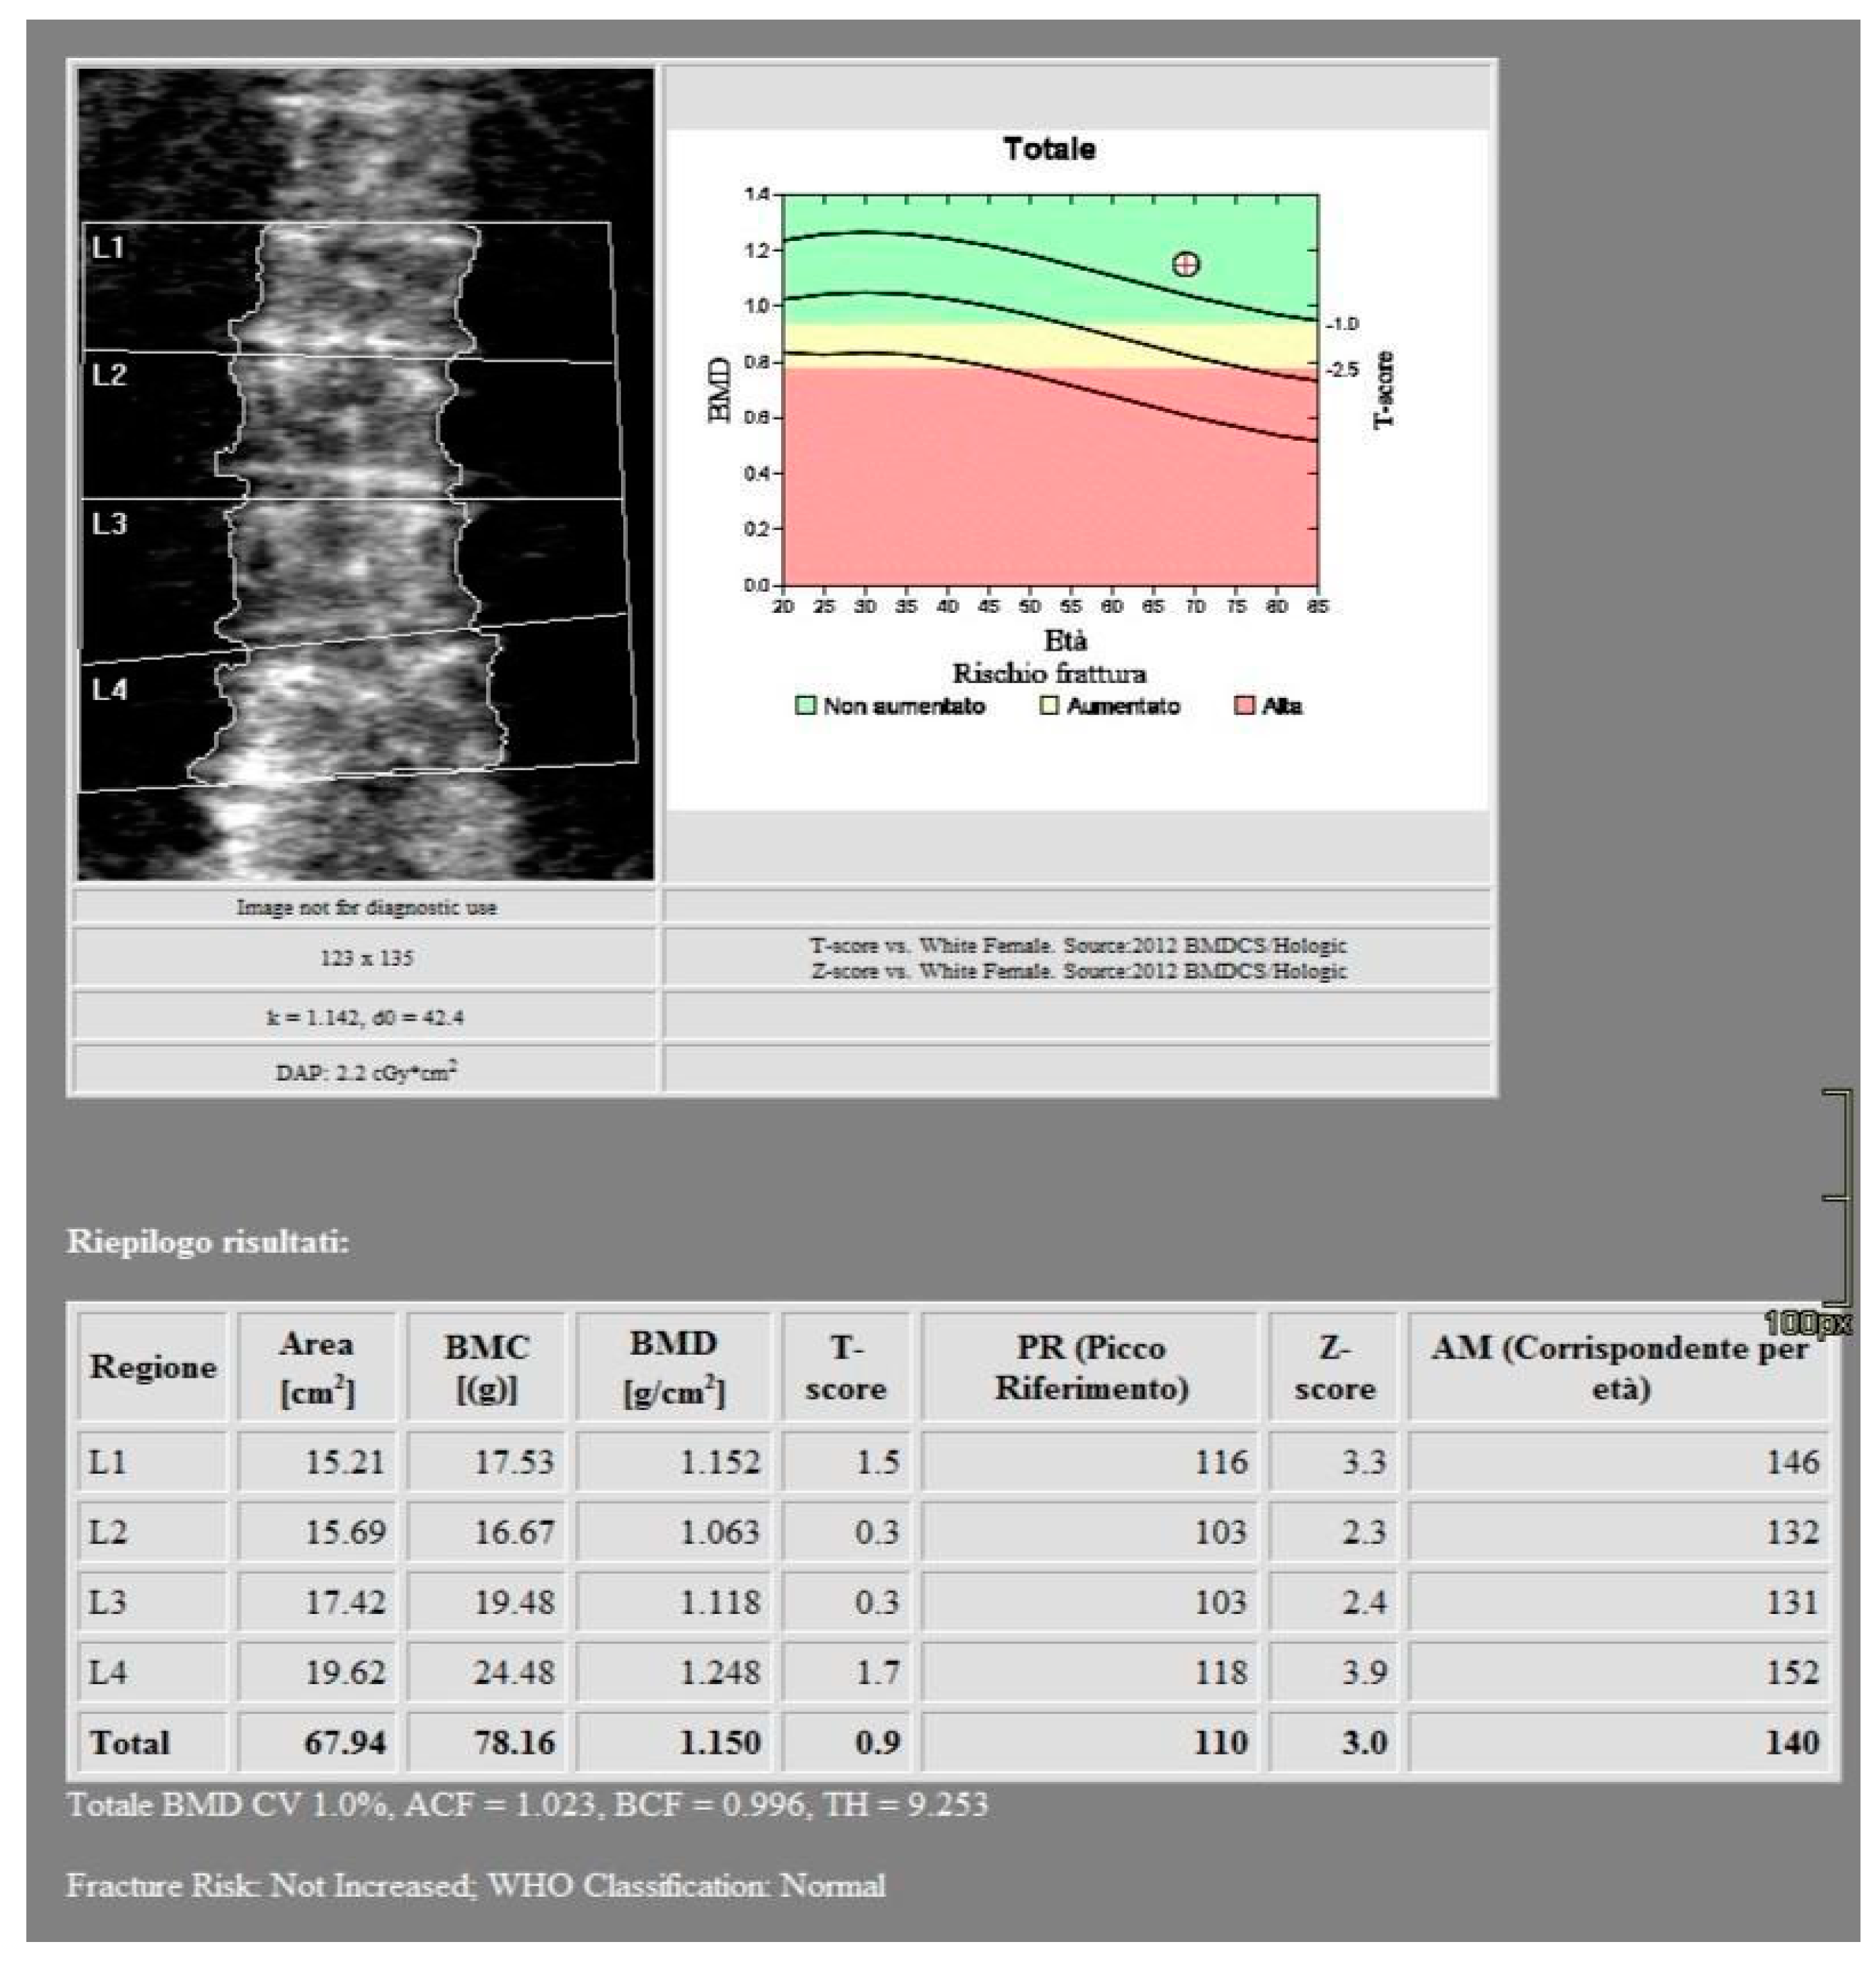

All images were acquired using a 256-slice multidetector CT system with spectral imaging capability (Revolution, GE Healthcare, Chicago, USA) using a 1.0 mm slice thickness, tube voltage of 80-140 kVp, and tube current of 200 mA (Dose Right automatic exposure control system). The CT data were reconstructed with GSI data, and MPR reconstructions were performed in coronal and sagittal planes. DXA scans were performed using a bone densitometer (Discovery A, HOLOGIC, USA) for the lumbar vertebrae (L1 to L4) and femoral neck (Figure 1 and Figure 2).

Figure 1. DXA measurements on the lumbar vertebrae.

Figure 2. DXA measurements on the femoral neck.

The baseline characteristics of the 51 patients participating in the study are presented in Table 1 and Table 2. According to the BMD measurement on DXA, 15 participants were diagnosed in osteoporotic range in the lumbar area and 15 participants in the hip area. 27 participants were identified in the osteopenic range in the lumbar area and 24 participants in the hip area. 9 subjects were classified in the normal range in the lumbar area and 12 subjects in the hip area.

For the lumbar vertebrae the mean BMD and T-score on DXA images were 0.648 g/cm2 and -3.66 for the osteoporosis group, 0.855 g/cm2 and -1.73 for the osteopenic group and 1.02 g/cm2 and -0.83 for the normal group, respectively (Figure 5). There was a significant difference among the osteoporosis, osteopenic and normal groups in BMD and T-score (all p < 0.001). The mean HAP value on DECT images was 144.86 mg/cm3 for the osteoporosis group, 162.49 mg/cm3 for the osteopenic group and 139.57 mg/cm3 for the normal group (p= 0.2591) (Table 1). Bland-Altman analysis revealed a bias of 0.09, with 95% limits of agreement from −1.6 to 1.8 (p = 0.4) (Figure 6).